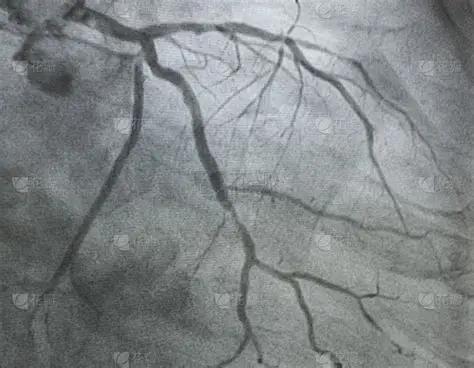

发烧能不能做冠脉造影?要看具体病情而定。如果目前病情相对稳定,做冠脉造影(或者支架手术)只是为了诊断或者常规治疗,则不建议做。在发烧期间做冠脉造影可能 会引起感染扩散,做冠脉造影会增加全身感染的风险,通常不建议。 如果是紧急情况,比如说急性 ST 段抬高型心肌梗塞,立即做。这时候开通血管挽救濒临崩溃的心脏供血至关重要,时间就是心肌,时间就是生命,尽早开通血管是挽救生命、保护心脏功能的首要任务。此时,发烧带来的风险远低于心肌持续坏死带来的心脏骤停、心衰的风险。所以在紧急情况下,该做还是得做。 总结一下,就是不紧急的情况,要等感染控制以后再做。紧急情况下,比如急性 ST 段抬高型心肌梗塞时,尽快做。